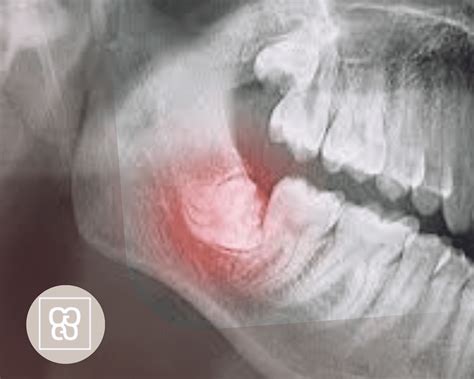

El diagnóstico radiológico es, junto con la exploración clínica, una prueba absolutamente esencial. En la mayoría de los casos, sobre todo en ausencia de una relación directa entre las raíces y el conducto dentario inferior, una ortopantomografía (OPG) y/o una radiografía intraoral serán suficientes para obtener la información necesaria. De no conseguir información concluyente con estas imágenes se puede recurrir a técnicas de imagen tridimensionales como la tomografía volumétrica digital (TVD) o la tomografía computarizada (TC). Dado que no se ha demostrado un beneficio terapéutico claro con la obtención de imágenes tridimensionales preoperatorias se recomienda no incluir estos procedimientos de forma sistemática en los estudios diagnósticos.

Lesiones Nerviosas

La posibilidad de lesión del nervio dentario inferior y del nervio lingual después de la extracción de los terceros molares inferiores forma parte sin duda de las complicaciones de las que es obligatorio informar al paciente antes de la intervención. Estas complicaciones pueden provocar serias molestias al paciente dependiendo de si son pasajeras o permanentes. Se estima que la incidencia de trastornos de sensibilidad permanentes asociados a una lesión del nervio dentario inferior es de aproximadamente un 1% y de aproximadamente un 0,4% en el caso del nervio lingual.

La relación anatómica de las raíces dentarias con el conducto dentario inferior o la tabla lingual es decisiva en este caso. Hatano et al propusieron la extracción parcial de los terceros molares (coronectomía) para evitar las lesiones nerviosas. Esta intervención consiste en extraer sólo la corona del diente, seccionado en el límite amelocementario, y conservar la raíz in situ. Sin embargo, en este estudio hasta el 4% de los pacientes tuvo que ser sometido a la extracción de los fragmentos radiculares residuales como consecuencia de inflamaciones postoperatorias. Se observó una migración de las raíces en el 30% de los casos. Por estos motivos y de acuerdo con los conocimientos actuales, la coronectomía no puede considerarse un método aceptado.